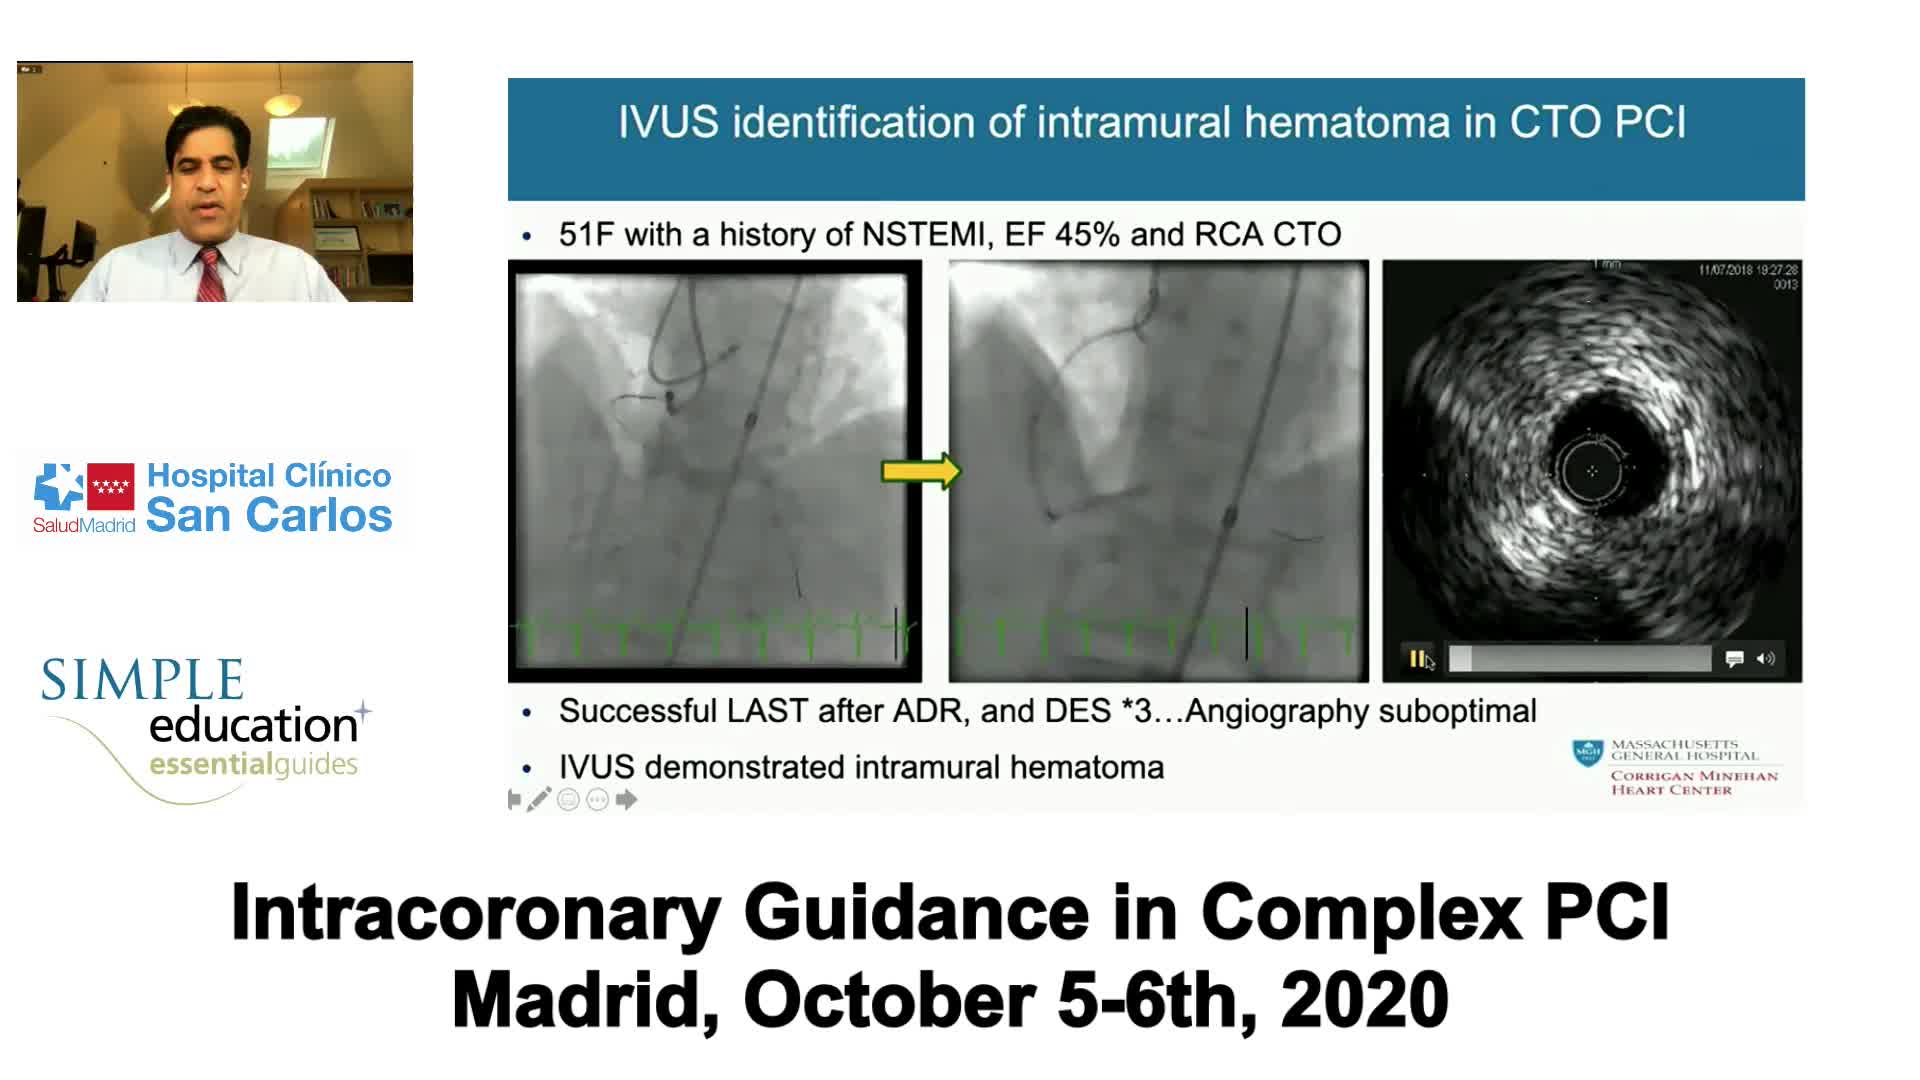

Complex PCI eCourse Madrid Day Two

Advanced PCI Course Content

Intracoronary guidance in acute coronary syndromes - Dr Hernan Mejia-Renteria